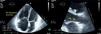

for assessment of RV contractile reserve: in apical 4-chamber view, RV area in diastole (Figure 1) and in systole (to calculate right ventricular fractional area change [RVFAC]), tricuspid annular plane systolic excursion (TAPSE) at the level of the RV free wall, S-wave velocity (with tissue Doppler of the basal segment of the RV free wall), and left ventricular outflow tract (LVOT) velocity-time integral (VTI) (Figure 2). In parasternal long-axis view, LVOT diameter (Figure 1) was assessed only at rest, considering that this dimension does not change with exercise. Stroke volume index (SVI) was calculated on the basis of LVOT diameter, LVOT VTI and BSA.

Figure 2.Echocardiographic parameters of right ventricular contractile reserve in a pulmonary hypertension patient at rest (left) and at peak exercise (right); top – S-wave velocity; middle – TAPSE; bottom – LVOT VTI (used to calculate stroke volume index). LVOT VTI: left ventricular outflow tract velocity-time integral; TAPSE: tricuspid annular plane systolic excursion.